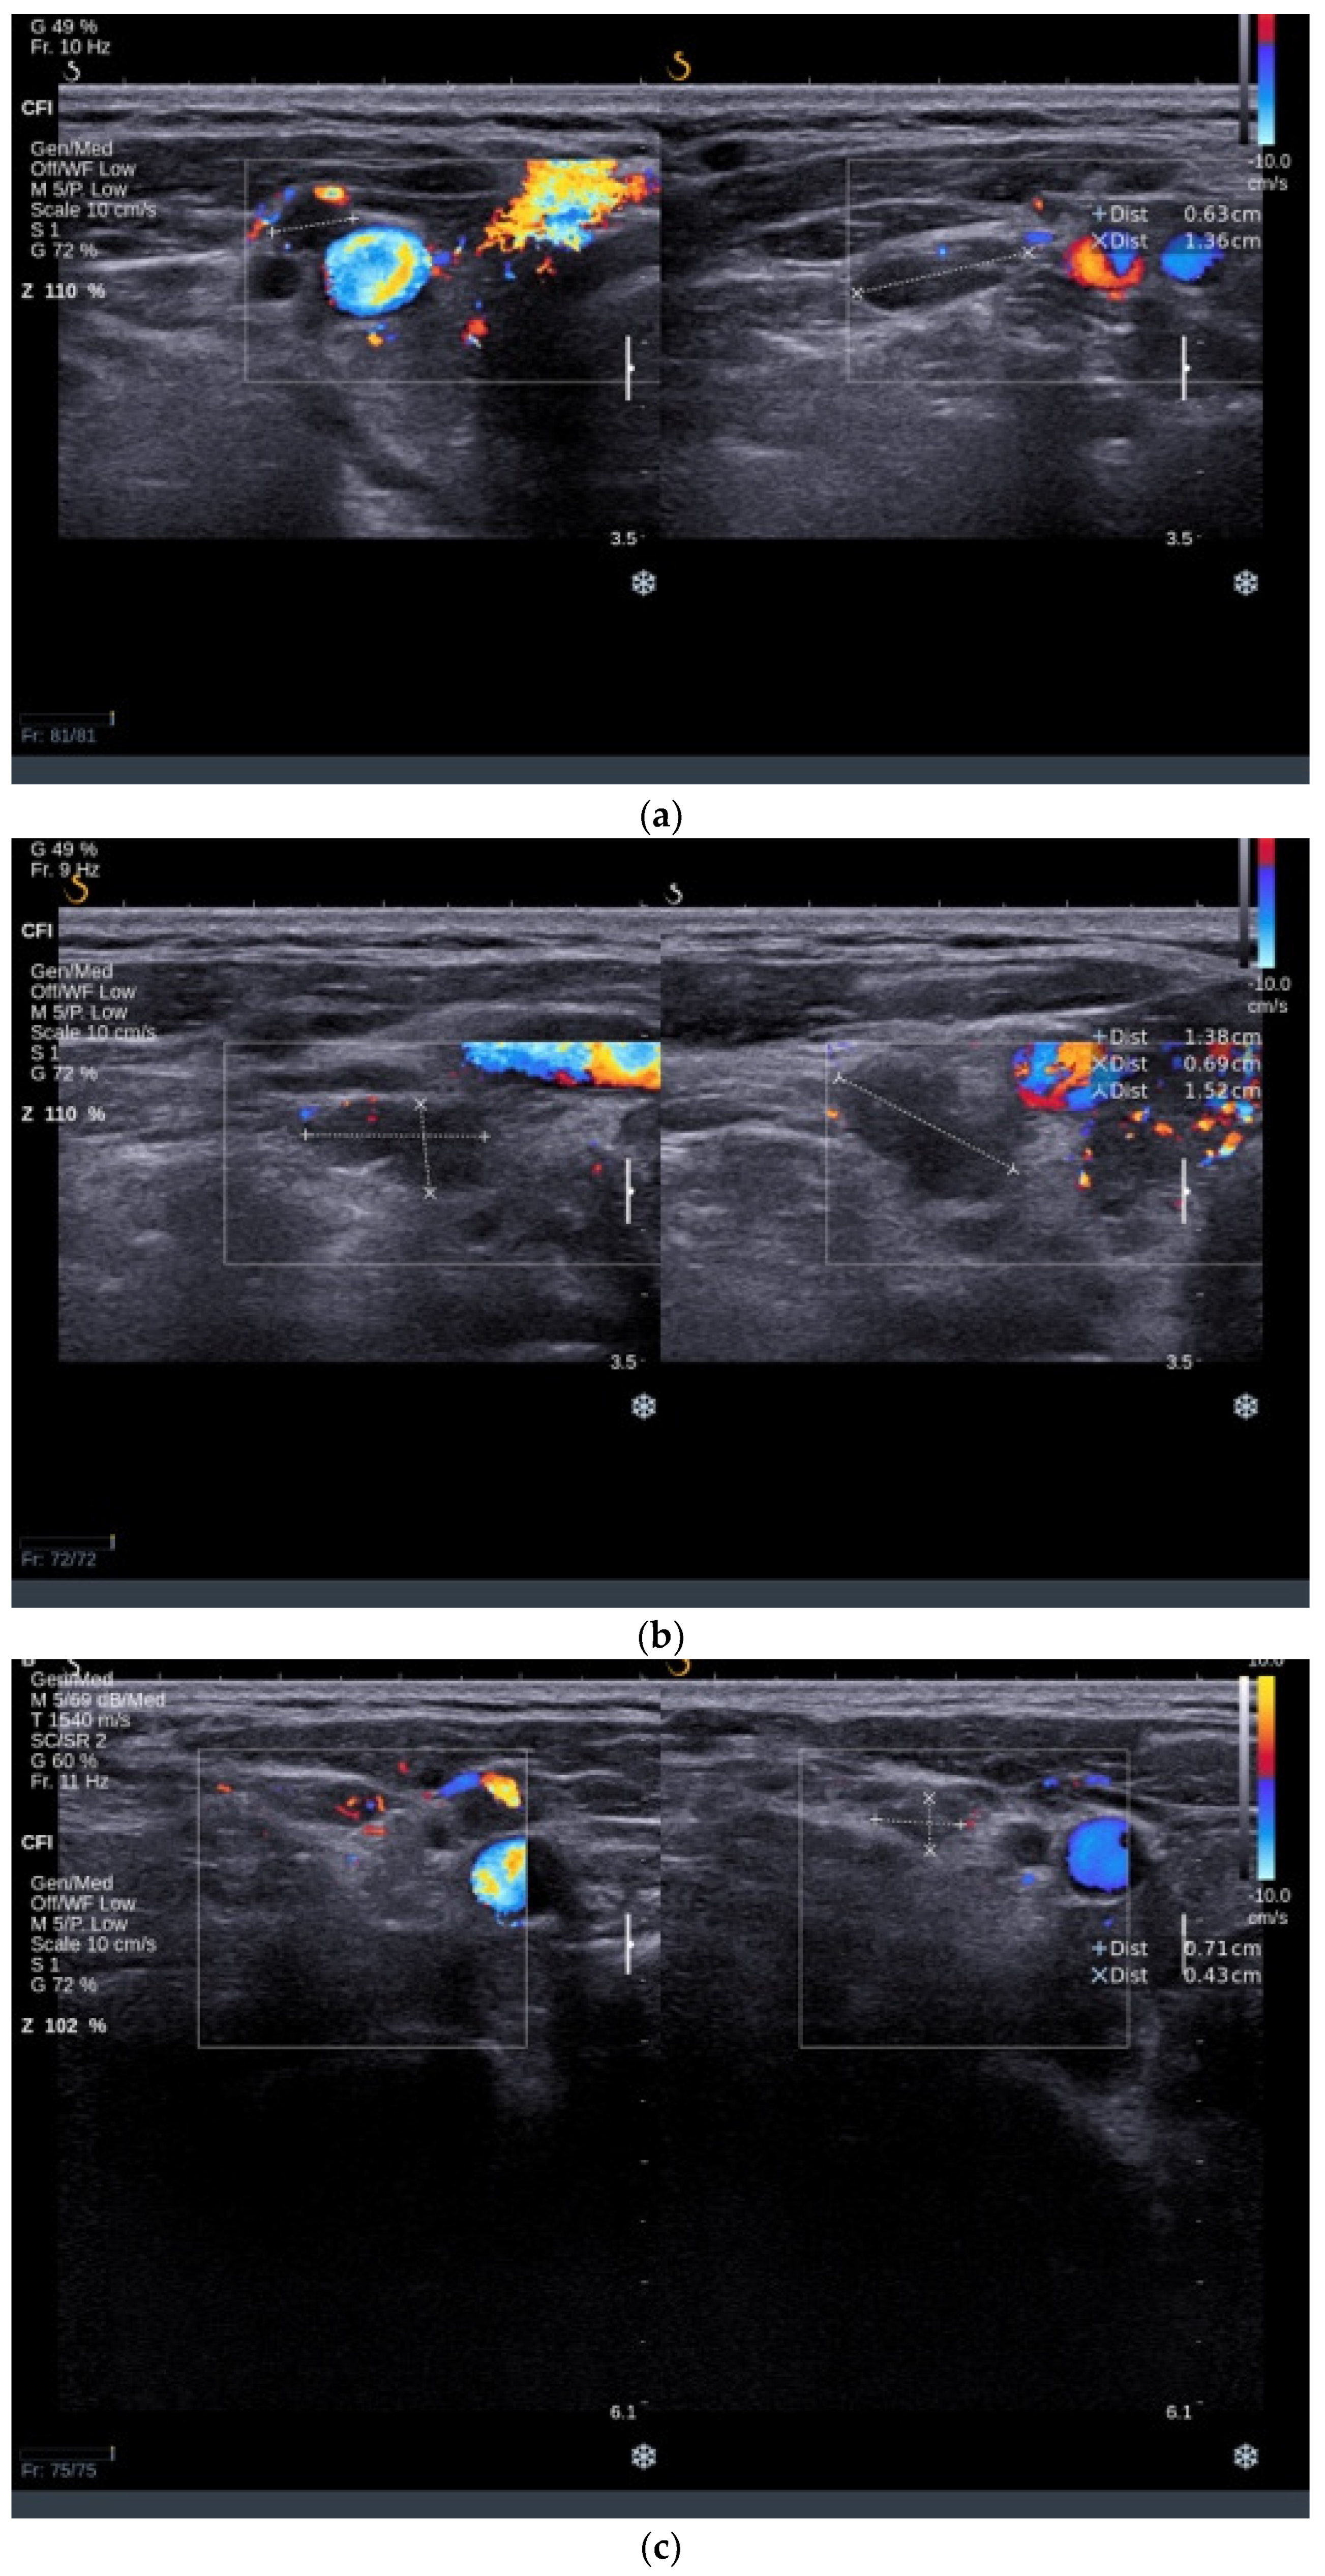

3.3.2. Thyroid Ultrasound